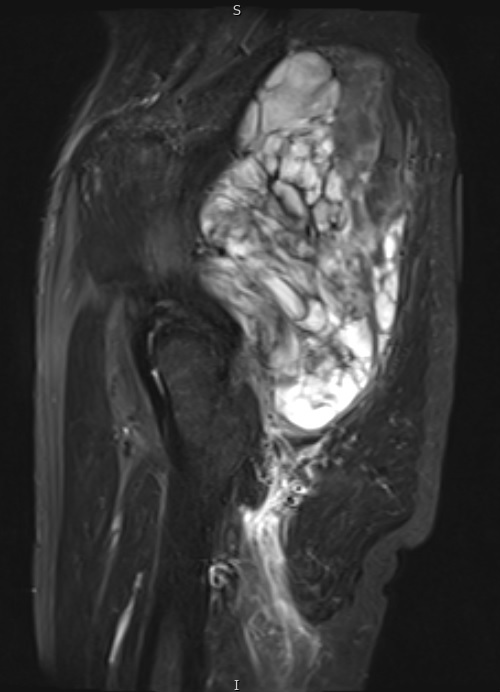

Fig. 1 & 2 Magnetic Resonance Image shows a large heterogeneous mass in the left gluteal region with low intensity signal on Axial (Fig. 1) and Coronal (Fig. 2) T1-weighted images admixed with some high signal areas indicative of fatty tissue. Higher intensity signal is visible compatible with hemorrhage or necrotic tissue. The mass involve the central portion of the left iliac bone.

Fig. 3 Axial fat suppressed T2-weighted MR image demonstrates a large heterogeneous mass with multiple thick internal trabeculations. Fatty areas suppress on T2 weighted fat suppressed areas

Fig. 7 & 8 Magnetic Resonance Image shows a large heterogeneous mass in the right thigh with low intensity signal on Axial (Fig. 7) and Coronal (Fig. 8) T1-weighted images admixed with high signal areas. The high signal areas represent low grade fatty tissue and low signal the dedifferentiated areas. Higher intensity signal is visible compatible with hemorrhage or necrotic tissue.